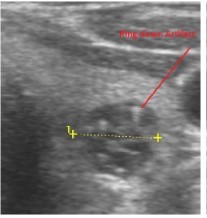

Figure 5.Ring down artifact of colloid nodule

Ring down artifact of colloid nodule